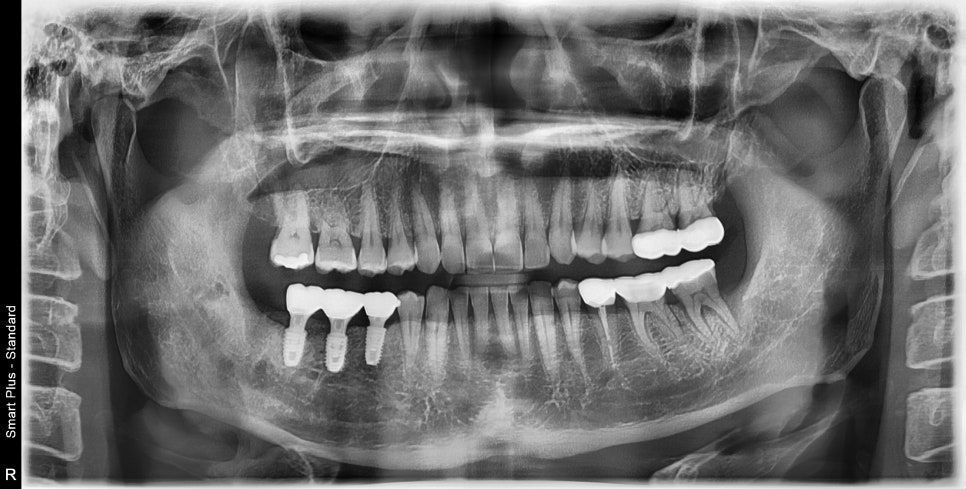

처음 내원후 5달이 지난 후 재내원

5달이 지난 어느날 내원해주셨는데

처음 내원때 사진보다 치아 주변 뼈가 더 많이 흡수가 되어있었습니다.

초기 진단과 다르게 임플란트가 들어가야할 공간에 뼈가 많이 흡수되어

치조골이식술을 한다해도 발치날 수술까지는 무리였습니다.

욕심내지 않고 주변 뼈의 볼륨을 회복 시킨후 수술하기로 했습니다.